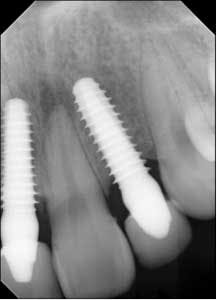

Implant sites were curetted well, then disinfected with Chloramine-T saturated gauze, followed by irrigation with 2% chlorhexidine and water. Bone grafting was not deemed necessary. Both implants No. 8 and No. 10 were replaced with TRX-OP 4.5 x 13 mm (Fig. 5). The patient was informed that because implants placed into previously failed sites have a lower success rate, absolute adherence to postoperative instructions was critical to any chance of success (4). Instructions were once again given to follow dietary restrictions and take the antibiotics as prescribed. The patient was seen six weeks postoperatively (Fig. 6) and set to have the final prosthesis inserted six months post-reimplantation.Fig. 5: No. 8 and No. 10 — implants replaced by 4.5 x 13 mm and retemporized.

Fig. 6: Postoperative six weeks later.The patient returned for a follow-up eight months later (Fig. 7) and claimed she was careful not to bite into anything with her front teeth and wanted to know if they could be restored with permanent crowns. Impressions were taken and sent to the lab for fabrication of implant crowns. One year post-insertion, the final crowns and radiographs were taken (Figs. 8 and 8a).